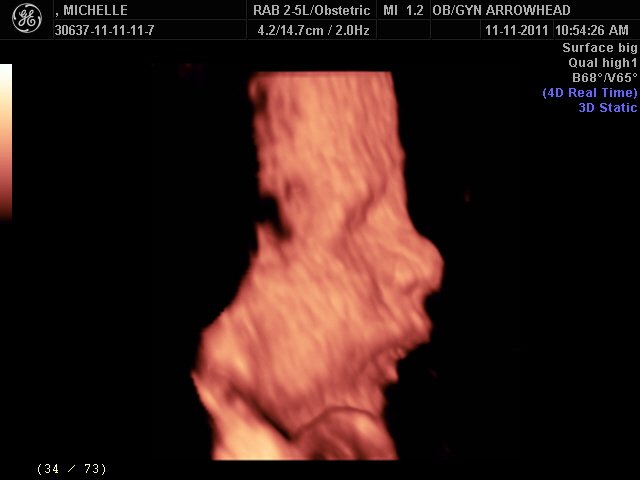

We offer complimentary 3D/4D Ultrasounds to all our OB patients around 30 weeks! The following photos are some examples of our work, shown with permission from our patients.